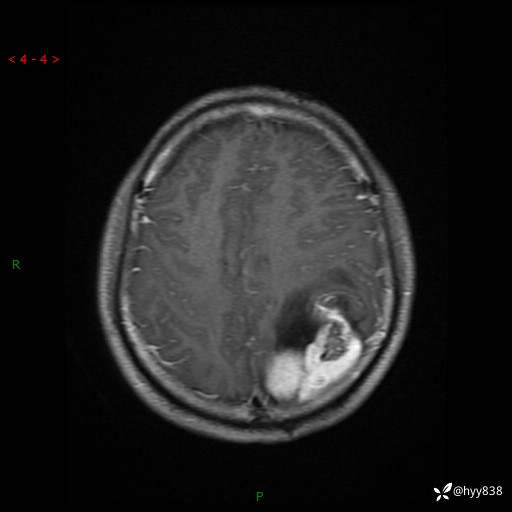

病例年轻小伙,头痛伴呕吐半年,渐进性加重1月。疑难病例,第一次见--结果公布~

性别:男

年龄:21岁

简要病史:头痛伴呕吐半年,渐进性加重1月

颅脑MRI平扫+增强